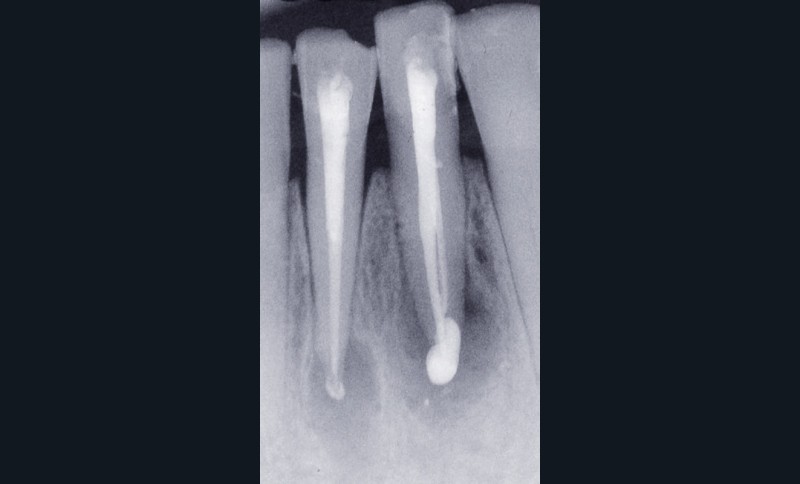

La troisième éventualité concerne le dépassement de matériau d’obturation canalaire (fig. 5) ou d’autres corps étrangers provoquant une réaction immunogène.

La présence d’éléments étrangers piégés dans le périapex au cours du traitement endodontique peut entretenir la lésion alors appelée granulome à corps étranger. Ainsi, même biocompatibles, des matériaux comme la gutta percha peuvent retarder la cicatrisation apicale [16], et ce d’autant si le cône de gutta percha ne présente pas toutes les garanties d’asepsie préalable ou s’il est contaminé par la présence de talc ou de poudre de latex provenant des gants. Sjögren et coll. [38] décrivent deux cas de figure. Si les éléments extrudés de gutta percha sont volumineux, ils seront encapsulés par une membrane collagénique. A contrario, si les particules sont fines, situation plus défavorable, elles induisent une réponse localisée intense, caractérisée par la présence de macrophages et de cellules géantes multinucléées à l’origine même de l’initiation de la lésion apicale. D’autres éléments néfastes à la guérison apicale peuvent être retrouvés. Ainsi, des particules végétales d’origine alimentaire peuvent être introduites dans le système endocanalaire si celui-ci est en contact avec la cavité buccale comme cela peut être le cas lors d’un traumatisme important ou d’une dent laissée ouverte. D’autres éléments extrinsèques peuvent être importés au cours de la préparation ou de l’obturation canalaire, comme des particules d’amalgame, de résine composite ou d’obturation temporaire. D’autres particules, par exemple les fibres de cellulose piégées lors du séchage canalaire à l’aide de pointes de papier ou issues des cotons éventuellement employés en interséance, peuvent contrarier la cicatrisation. Ces éléments sont en effet difficilement dégradés par les cellules de défense de l’hôte et peuvent même favoriser la croissance de biofilms bactériens à leur surface.